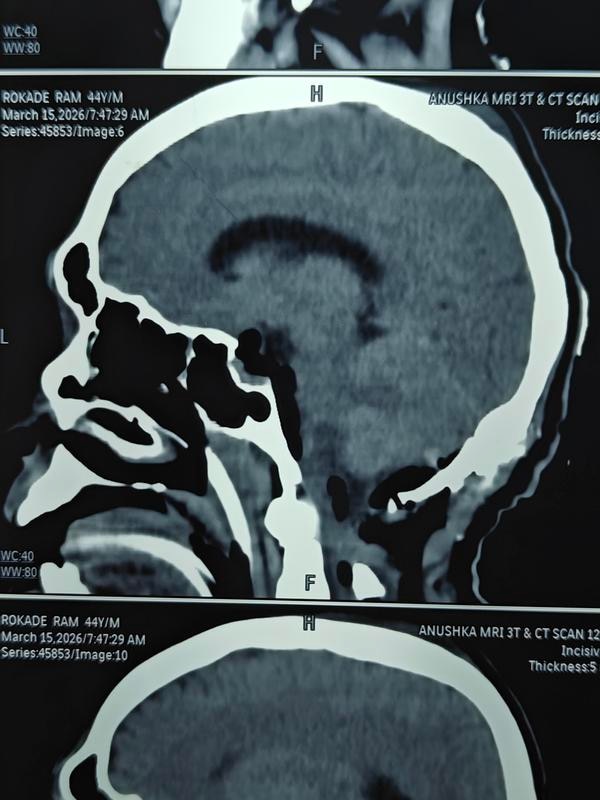

How serious is spinal surgery?Back surgery can carry higher risks than some other types of surgery because it is done closer to the nervous system. The most serious of these risks include paralysis and infections. Even with a successful surgery, the recovery time can be long.